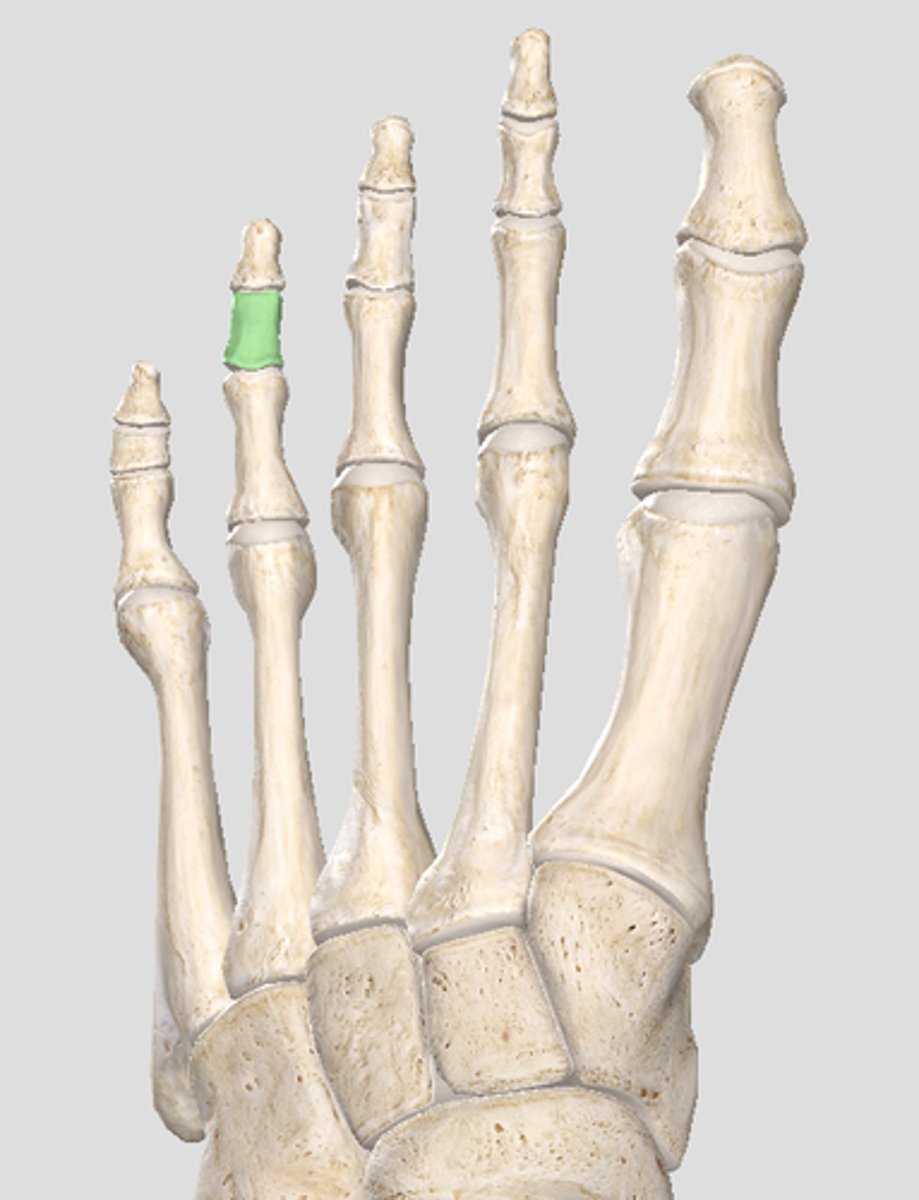

Proximal phalanx of digit 2

Middle phalanx of digit 2

Distal phalanx of digit 2